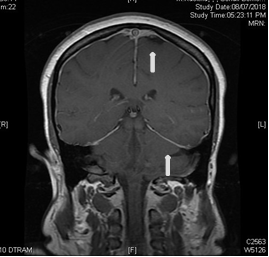

She had MRI brain and C spine with contrast, (Figure 1) a lumbar puncture after imaging, intravenous pain medication, dexamethasone per os, and was positioned supinely. Her brain MRI and C spine showed signs of low intracranial pressure with DME; see in Figure 2. She initially had a traumatic and dry LP with Glucose 5.68, raised protein of 3672 mg, 54000 red cells, 43 white cells and xanthochromia was positive.

Figure 1 white arrow pointing to contrast enhancement.

Figure 2 white arrows pointing to contrast enhancement.